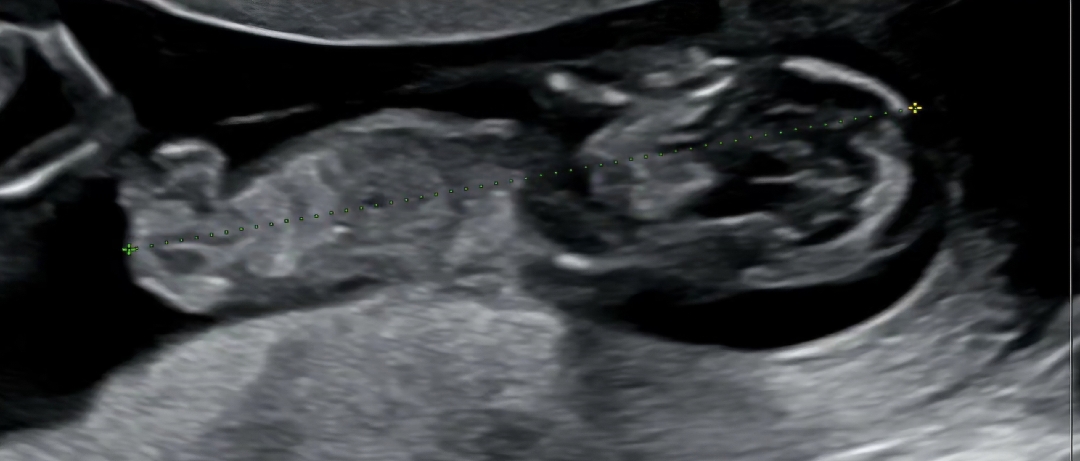

각도법.. 봐주실수있을까요 !

성별이 궁금합니다 각도법 도저히 모르겟어서 부탁드려요!